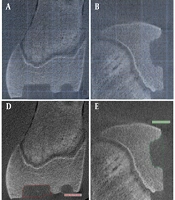

Diagnostic Accuracy of MRI-Based Dixon and T2 Localization Techniques for Imaging Severity and Progression in Thyroid-Associated Ocular Diseases